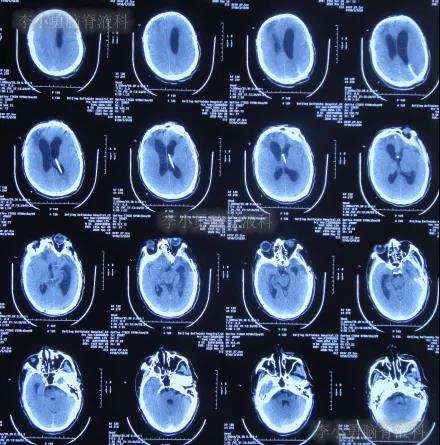

为求进一步有效治疗,于第1家医院出院后19天即2019年12月10日,住入第2家的北京某解放军的三甲医院,入院次日查头颅CT(图-14)后认为是脑积水。

图-14:2019年12月11日头颅CT